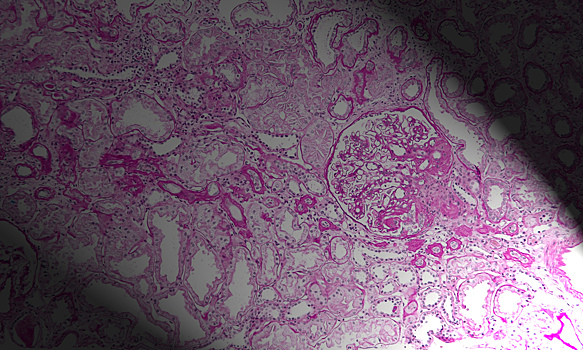

Ислледователи из НИИ физико-химической биологии МГУ и Национального медицинского исследовательского центра акушерства, гинекологии и перинатологии доказали эффективность митохондриально-адресованного антиоксиданта SkQR1 в борьбе с почечной недостаточностью у новорожденных крысят. Открытие может стать основой для разработки терапии почечной недостаточности у младенцев. Результаты работы опубликованы в научном журнале Antioxidants. Иммунная система новорожденных часто оказывается неспособной бороться с патогенными микроорганизмами. В результате так называемые «госпитальные» инфекции порой перерастают в системное воспаление — сепсис. Самое опасное последствие сепсиса заключается в отказе многих органов одновременно. Одни из первых отказывают почки. Российские ученые считают митохондриально-адресованный антиоксидант SkQR1 перспективным в борьбе с бактериальными инфекциями и их последствиями. Исследователи моделировали сепсис у новорожденных крысят с помощью инъекции липополисахарида клеточной стенки бактерий. Эта операция приводила к повреждениям тубулярных клеток почки. Трансписионная электронная микроскопия показала, что основные структуры, страдающими при действии липополисахарида (ЛПС) — это митохондрии. Нарушения митохондрий наблюдали уже через три часа действия ЛПС и достигали максимума к 24 часам. Из митохондрий высвобождались токсичные активные формы кислорода, в моче регистрировали высокое содержание белков-маркеров острого почечного повреждения. Введение антиоксиданта за три часа до индукции сепсиса защитило почки от повреждения, хотя в почечных канальцах все еще наблюдались отдельные клетки с нарушенными митохондриями. Гибель животных от сепсиса в группе получавших SkQR1 была значительно ниже, чем у контрольной группы. «Мы делаем вывод, что, хотя SkQR1 не смог абсолютно предотвратить нарушение структуры митохондрий, его антиоксидантные свойства помогли почке новорожденных сохранить свои функции», — сообщает соавтор работы Егор Плотников. Понравился материал? Добавьте Indicator.Ru в «Мои источники» Яндекс.Новостей и читайте нас чаще. Пресс-релизы о научных исследованиях, информацию о последних вышедших научных статьях и анонсы конференций, а также данные о выигранных грантах и премиях присылайте на адрес science@indicator.ru.